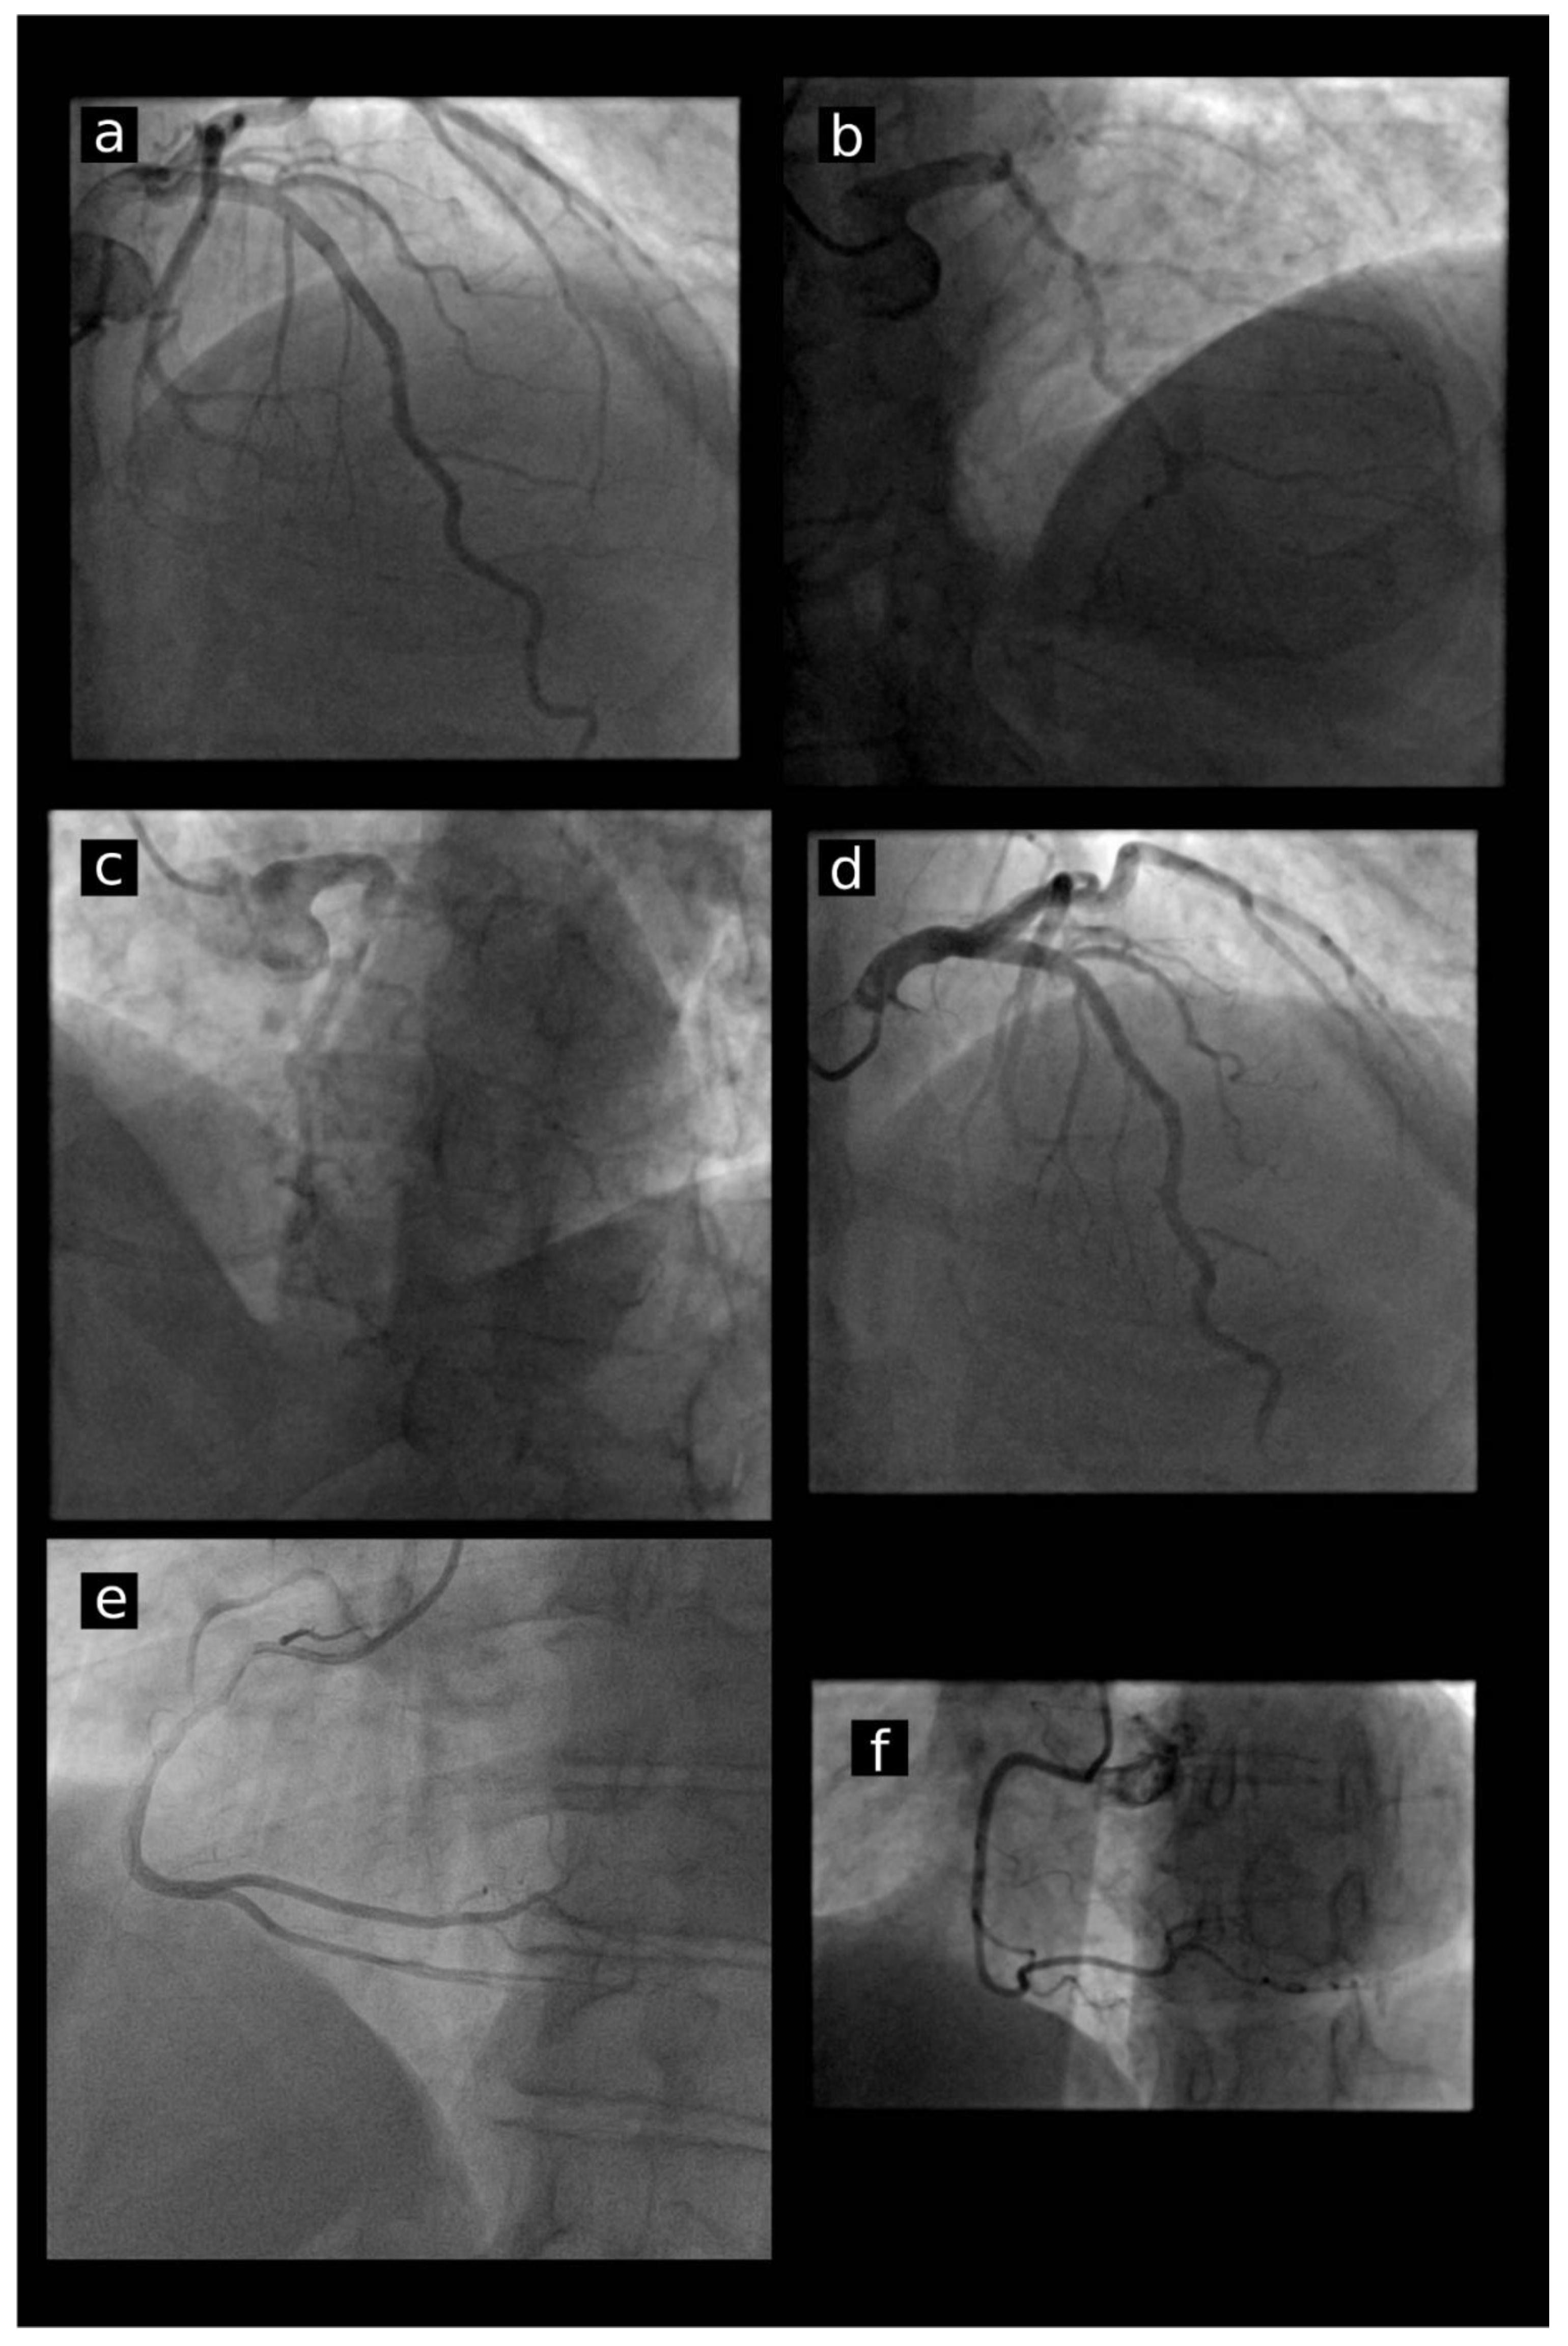

2. Materials and Methods

3.2. Ostial Stability and Engagement in Investigated Groups